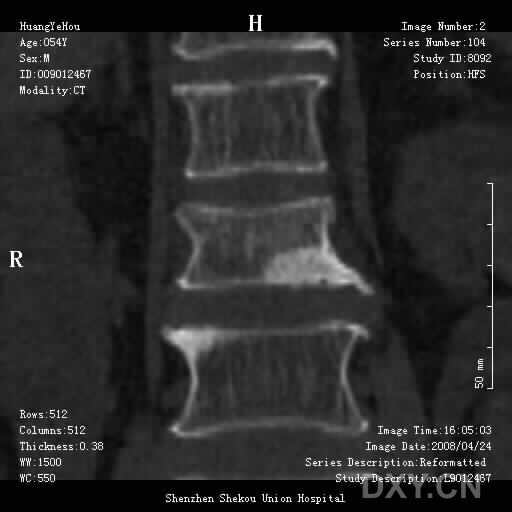

男,54岁,腰部外伤疼痛2小时!

1、腰3椎体压缩骨折

2、腰椎退行性变。

1.腰椎椎体压缩性骨折,  2. 退行性改变(局限性骨质密度增高.

前缘变窄;压缩骨折;椎体硬化征;退行性变